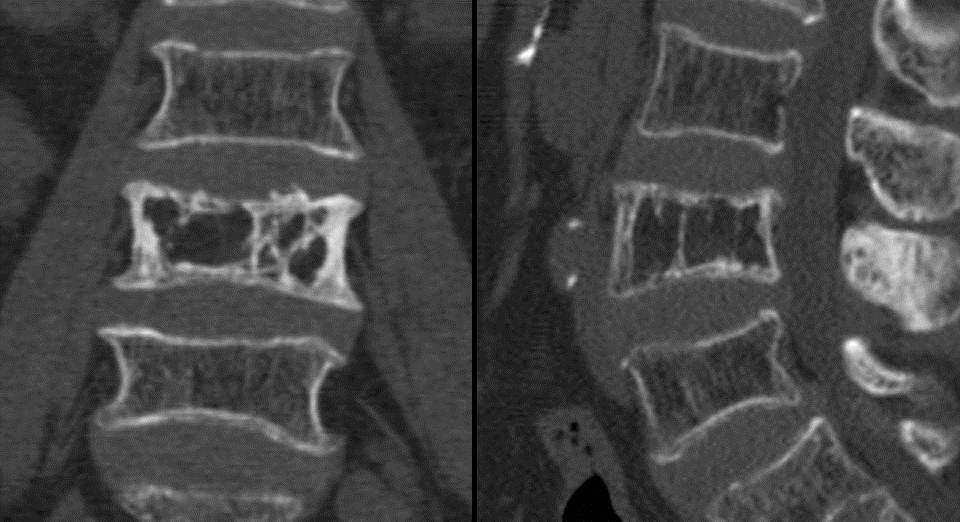

Imaging of Paget Disease of Bone and Its Musculoskeletal Complications Paget's Disease Vertebral Body Radiology radiography is the imaging modality of choice for the evaluation of suspicious skeletal regions in paget’s disease of bone. lateral radiograph of the upper thoracic spine reveals a densely sclerotic vertebral body (ivory vertebra) caused by paget disease (arrow). signs described of enlargement of the vertebral body, preservation of the bone marrow and thickened cortex of vertebral.. Paget's Disease Vertebral Body Radiology.

Imaging of Paget Disease of Bone and Its Musculoskeletal Complications Paget's Disease Vertebral Body Radiology radiography is the imaging modality of choice for the evaluation of suspicious skeletal regions in paget’s disease of bone. signs described of enlargement of the vertebral body, preservation of the bone marrow and thickened cortex of vertebral. sir james paget described the disease in 1877 as a chronic inflammatory remodelling disease of bones. spinal stenosis in. Paget's Disease Vertebral Body Radiology.